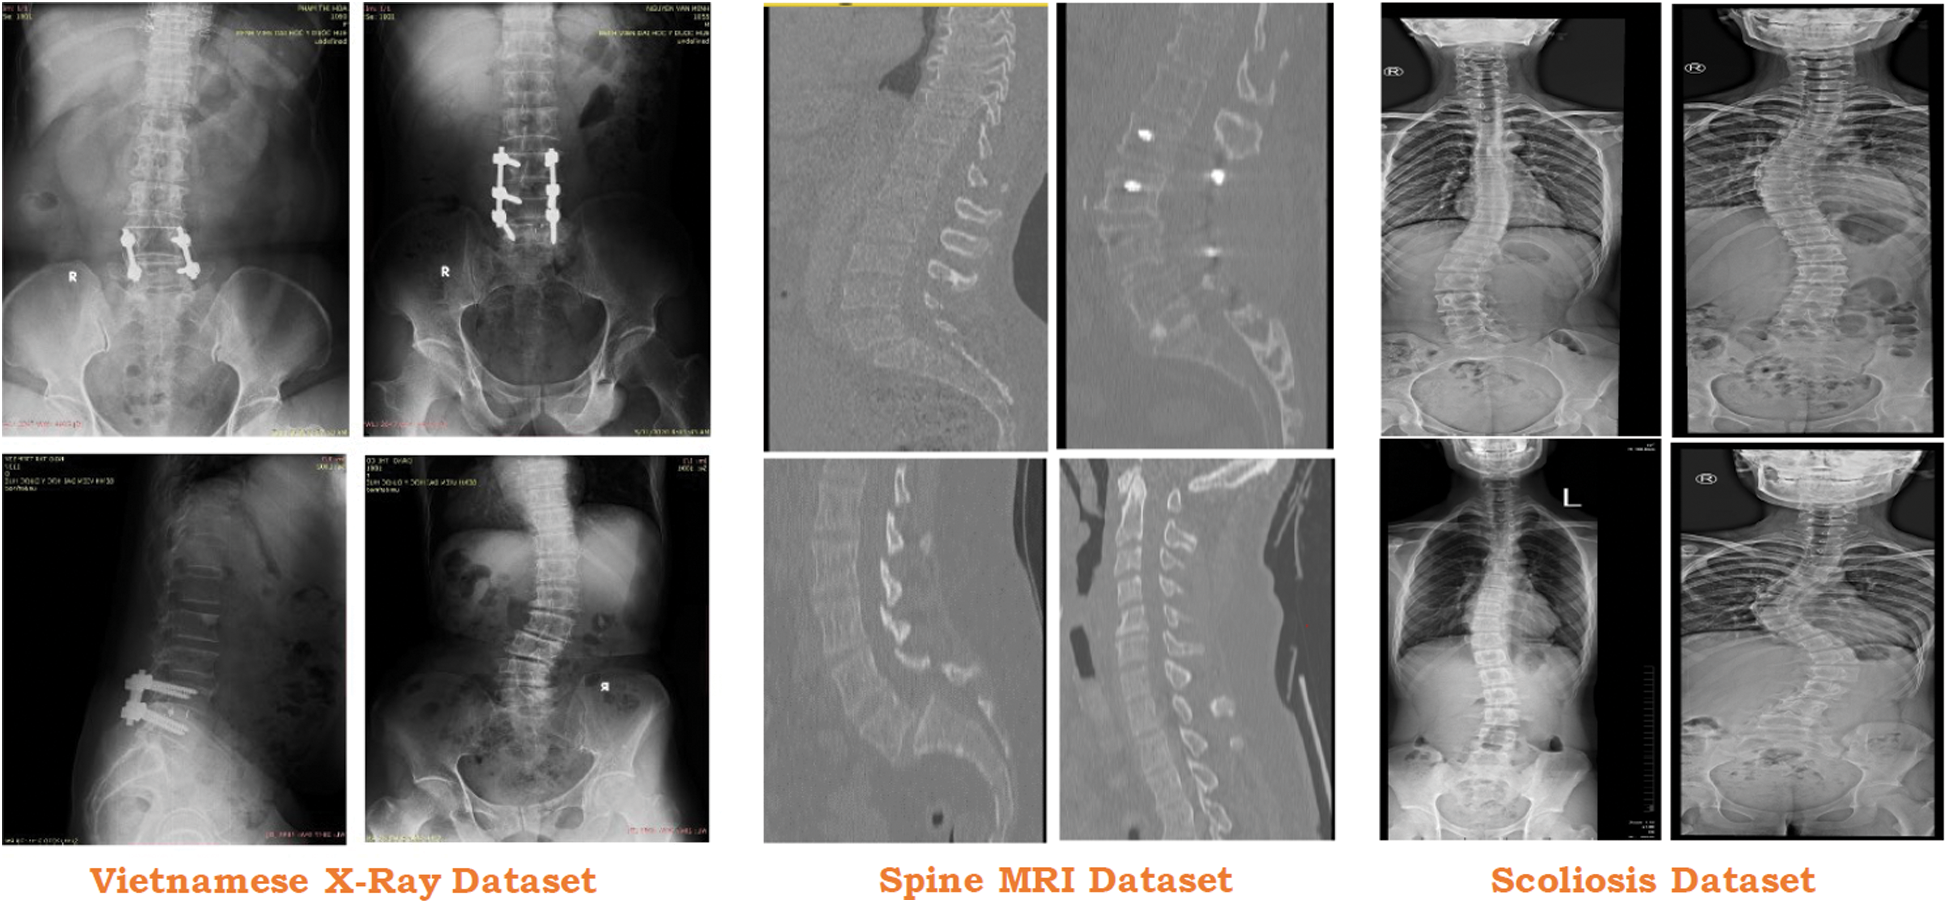

To test the proposed approach, we collected the data from 3 different sources which include one local Vietnamese hospital and two public repositories (see Fig. 6). Vietnamese hospital dataset only includes 200 DICOM images that are not enough for the proposed approach. To overcome this issue, two different ways are being deployed.

Figure 6: Usage of different dataset in the proposed study

Similarly, in the case of Scoliosis detection, the Vietnamese Dataset and MRI Dataset [57] are also limited and not enough to predict scoliosis in the X-Ray imaging. To increase the number of scoliosis X-Ray imaging in the dataset, some images [58] are used. This dataset contains 98 scoliosis x-ray imaging which is suitable for our system.

Tab. 4 represents the flow of dataset distribution in the proposed system. A total of 598 images have been used in the proposed system including 200 images, 300 images, and 98 images from the Vietnamese x-ray, MRI imaging, and scoliosis dataset respectively. 200 images in the Vietnamese x-ray are further divided into 140 images, 30 images, and 30 images for training, testing, and validation respectively. 300 images in the MRI-images are further divided into 210 images, 45 images, and 45 images for training, testing, and validation respectively. 98 images in the scoliosis are further divided into 68 images, 15 images, and 15 images for training, testing and, validation respectively.